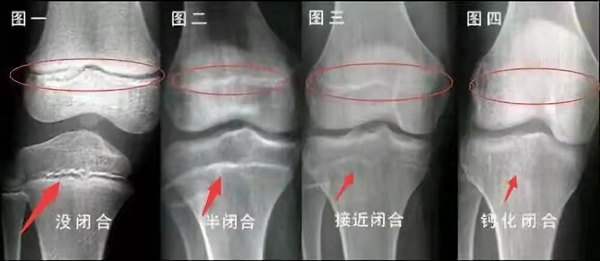

我們都知道,人體的高矮是由骨骼的生長(zhǎng)發(fā)育決定的,特別是下肢長(zhǎng)骨。長(zhǎng)骨呈長(zhǎng)管狀,在長(zhǎng)骨的兩端有一種專(zhuān)管骨骼生長(zhǎng)的骺軟骨,它與干骺端之間有一盤(pán)狀軟骨結(jié)構(gòu)稱(chēng)為骺板(線),在幼兒的X光片上表現(xiàn)為一條較寬的透光帶。 (見(jiàn)下圖)

未成年時(shí)隨著年齡的增加骺軟骨端不斷骨化,骨骼就不斷增長(zhǎng)。當(dāng)骨骺線完全閉合時(shí)骨骼就停止生長(zhǎng),個(gè)子也就不再增長(zhǎng)了。一般骨骺端完全閉合的年齡是18~20歲左右。